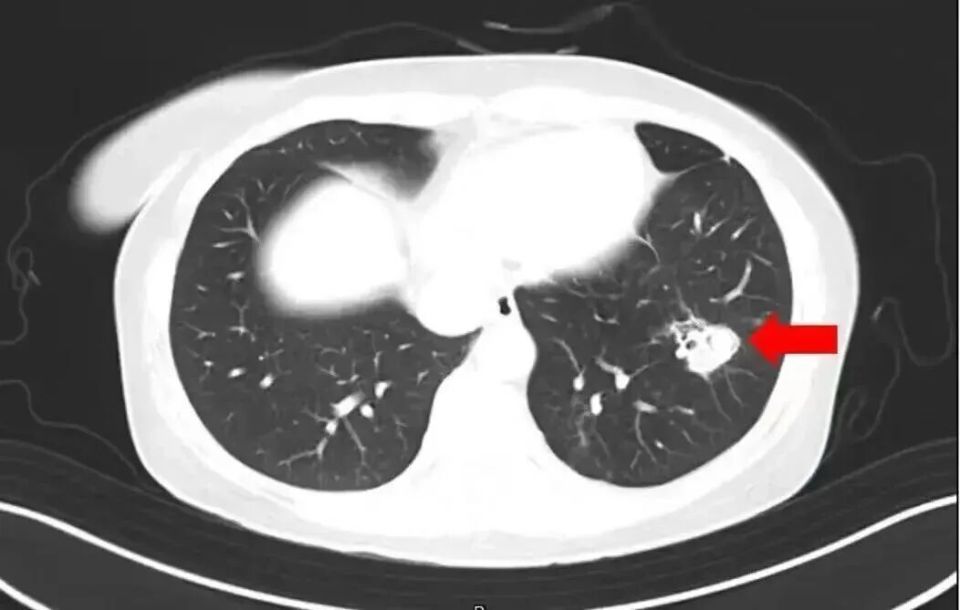

• 2025年1月,江苏扬州的张大爷为迎接春节开始大扫除,清扫过程中不慎吸入大量灰尘和霉菌孢子,导致哮喘发作。张大爷随即服用了常备的哮喘治疗药物,可症状反而逐渐加重。经检查,张大爷的肺部出现感染,确诊为肺曲霉病。

北京佑安医院感染综合科主任医师李侗曾介绍,对于免疫力低下的人,吸入了这些真菌,就会发病引起肺部的病变——曲霉肺炎。因为它是通过呼吸道感染的,进入血液后可以扩散到全身。大脑因为血供最丰富,所以也是真菌最容易侵犯的器官。